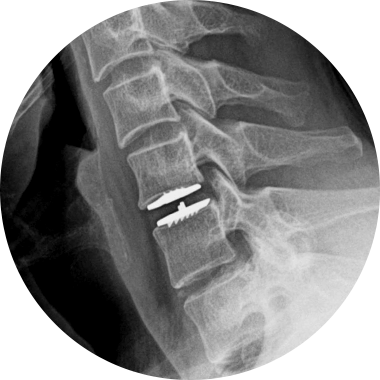

STEP 02

손상된 디스크 제거

STEP 03

인공디스크 삽입